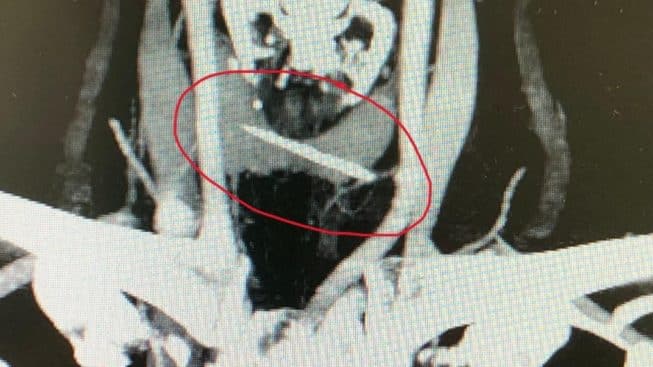

Una 54enne brindisina che durante un pasto aveva ingerito involontariamente un frammento di osso lungo 3,7 centimetri (rimasto bloccato a 5 millimetri dalla giugulare, nel tratto cervicale dell’esofago) è stata operata con successo al Policlinico di Bari per la rimozione del corpo estraneo dall’equipe di endoscopia digestiva e chirurgia ospedaliera: la donna si era rivolta dapprima al pronto soccorso dell’ospedale Perrino, lamentando dolori toracici e difficoltà di respiro. A seguito di Tac, vista la pericolosità della posizione dell’osso, è stata trasferita a Bari e operata d’urgenza. Dopo alcuni giorni di degenza e una graduale ripresa dell’alimentazione liquida, è stata dimessa senza aver riportato danni ulteriori.